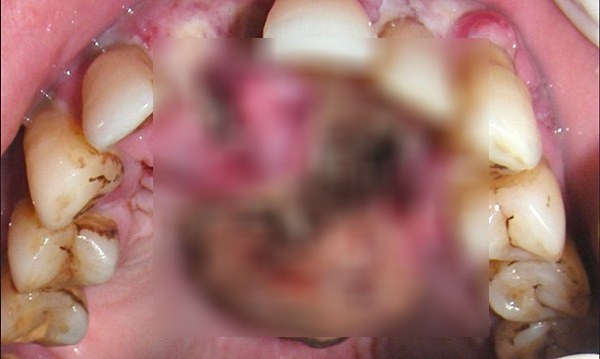

7. Noma โรคมะเร็งช่องปากซึ่งหลังจากเกิ